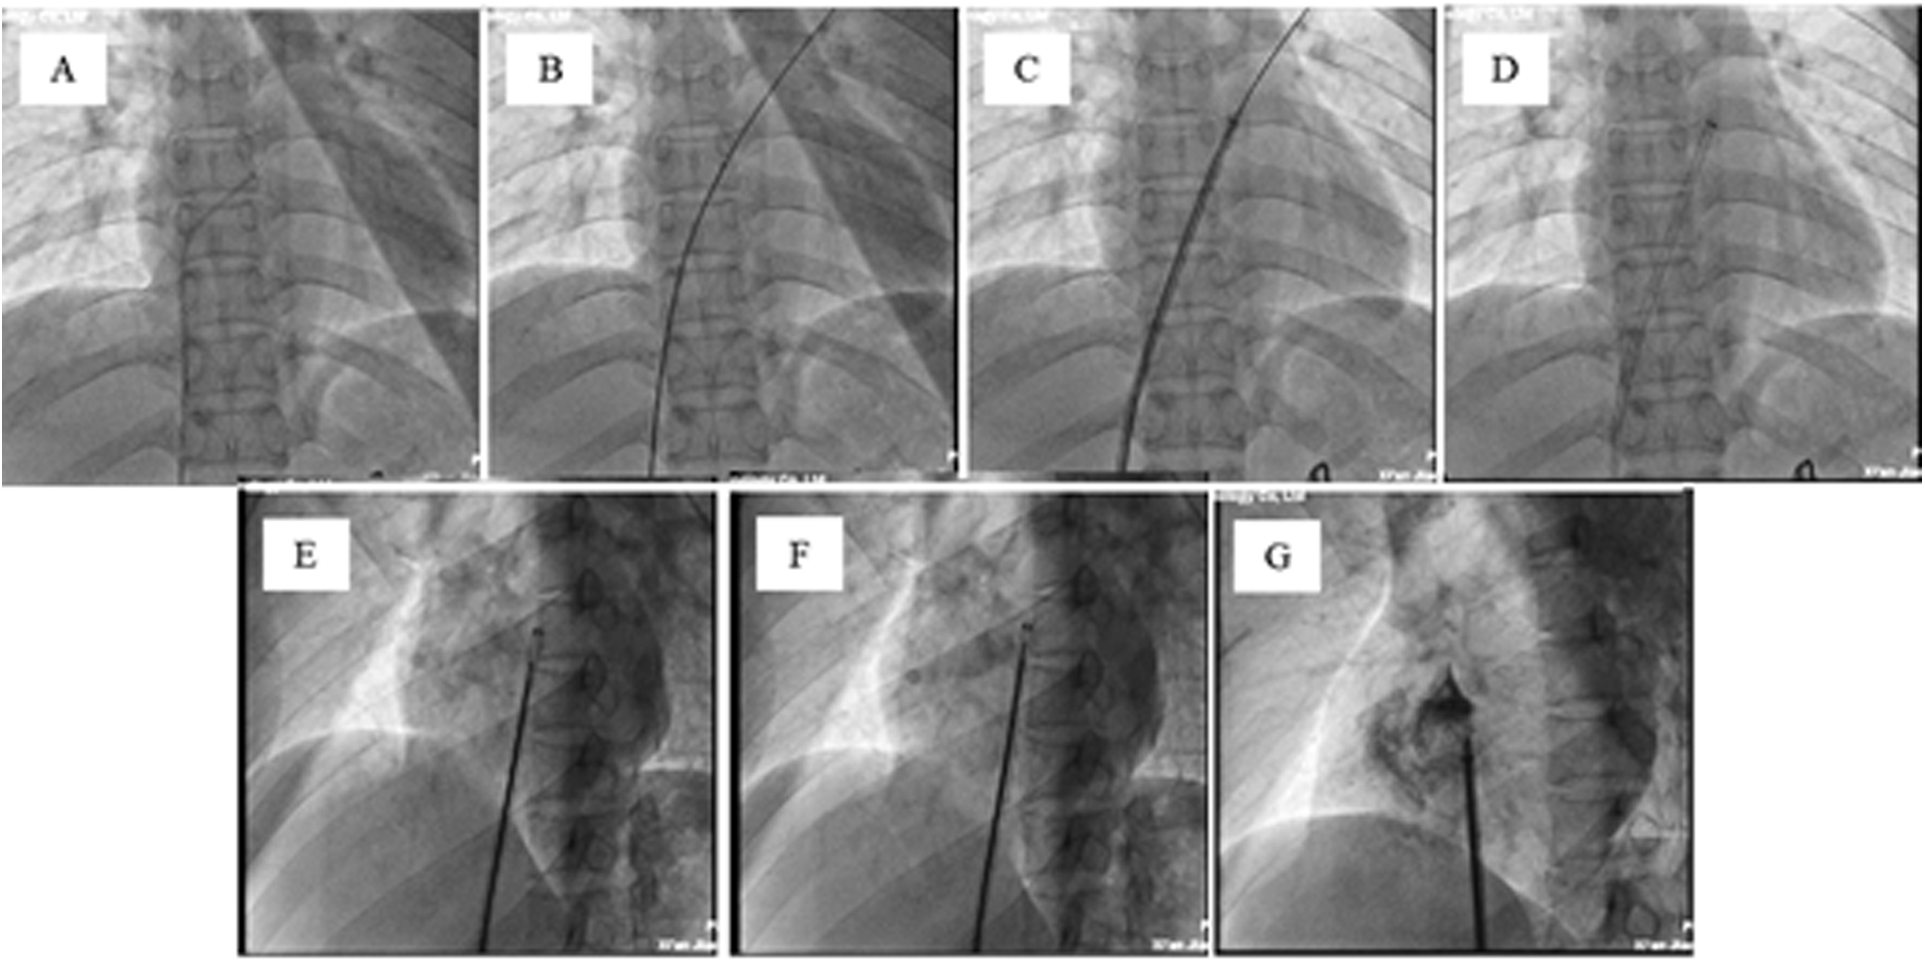

Figure 3

Transcatheter closure of the PFO with a biodegradable pansy® occluder. (A) A multipurpose (MP) diagnosticcatheter (6-Fr) is advanced over the wire to the base of the right atrium (RA). The catheter is directed towardthe interatrial septum (IAS), a maneuver that can be assisted by aligning the orientation of the MP catheter with the direction of theimaging element of the fossa ovale angiography. (B) A standard 0.035-inch J-tipped wire is advanced through the MP catheter across the PFO and into the left upper pulmonary vein (LUPV). (C) A 0.035-inch Amplatzer extrastiff guidewire (260 cm) is advanced over the MP catheter to the LUPV. Then, the delivery sheath is advanced over the 0.035-inch Amplatzer extra stiff guidewire to the left atrium. (D) The expansion sheath and the 0.035-inch Amplatzer extra stiff guidewireare withdrawn. (E) Under TTE guidance, the left disc of the occluder is opened and located in the left atrium. (F) Under TTE guidance, the right disc of the occluder is opened, and the occluder is located on the IAS. G. After the diluted contrast medium is delivered through the sheath, the occluder can be seen in good position, and the left and right discs are clearly separated.